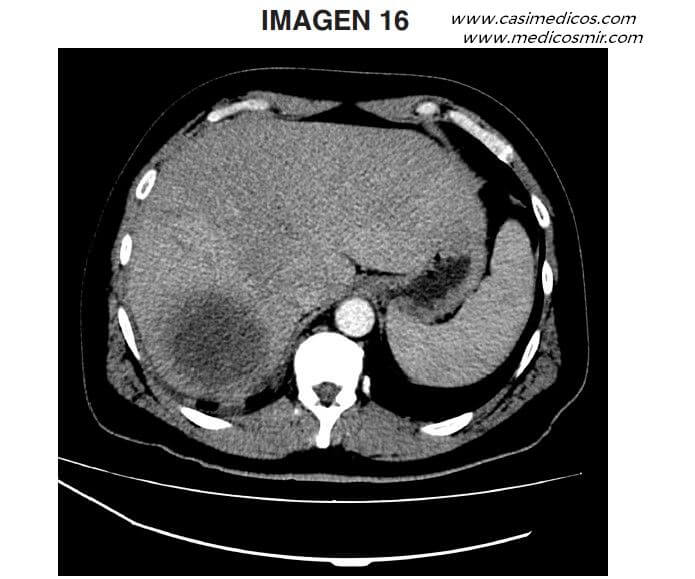

Pregunta 16

Pregunta vinculada a la imagen 16

Varón de 47 años sin antecedentes de interés que acude a urgencias por fiebre de hasta 39ºC con escalofríos y sudoración, de una semana de evolución, acompañada de dolor epigástrico y malestar general. Se realiza TC abdominopélvica con contraste endovenoso que se muestra en la imagen. ¿Cuál de los siguientes diagnósticos es más probable?:

- Absceso hepático

- Hemangioma hepático

- Hepatocarcinoma

- Hiperplasia nodular focal con necrosis en su interior.

Respuesta correcta: 1.

Comentario:

Esta pregunta podría responderse prácticamente haciendo caso omiso a la imagen dado que el paciente presenta una clínica infecciosa de 1 semana de evolución, lo que ya orienta a absceso, por encima de las otras opciones. Ciñéndonos a la imagen, nos encontramos con un corte de TC de hemiabdomen superior en una fase probablemente arterial tardía (el bazo presenta una mayor densidad global que el hígado debido a que el 80% de la vascularización de este proviene de la vena porta), donde se objetiva una lesión hipodensa en segmento VII, bien definida, sin realice periférico significativo. Los margenes de dicha lesión presentan una mayores densidad y bordes poco definidos que podrían traducir areas flemonosas. Estos hallazgos son compatibles con absceso hepático con áreas flemosas periféricas (respuesta 1 correcta). El hemangiona hepático típicamente se presenta como una lesión con realce periférico en fase arterial, que presenta relleno de contraste progresivo centrípeto en fases tardías (respuesta 2 incorrecta). El hepatocarcinoma suele asentar sobre hígados cirróticos (que se visualizan en TC con nodularidad del borde hepático así como hipodensidad difusa e heterogeneidad del parénquima, no presentes en este caso) y se identifica en la mayoría de los casos como una lesión mal definida con realce en fase arterial, siendo necesaria para su confirmación por TC un lavado de contrastes en fases tardías (respuesta 3 incorrecta). En cuanto a la hiperplasia nodular focal esta se demuestra con un realce brillante homogéneo en fase arterial (a excepción de una típica cicatriz central hipodensa). En fases tardías, la lesión se torna hipodensa y la cicatriz referida, hiperdensa. (Respuesta 4 incorrecta)